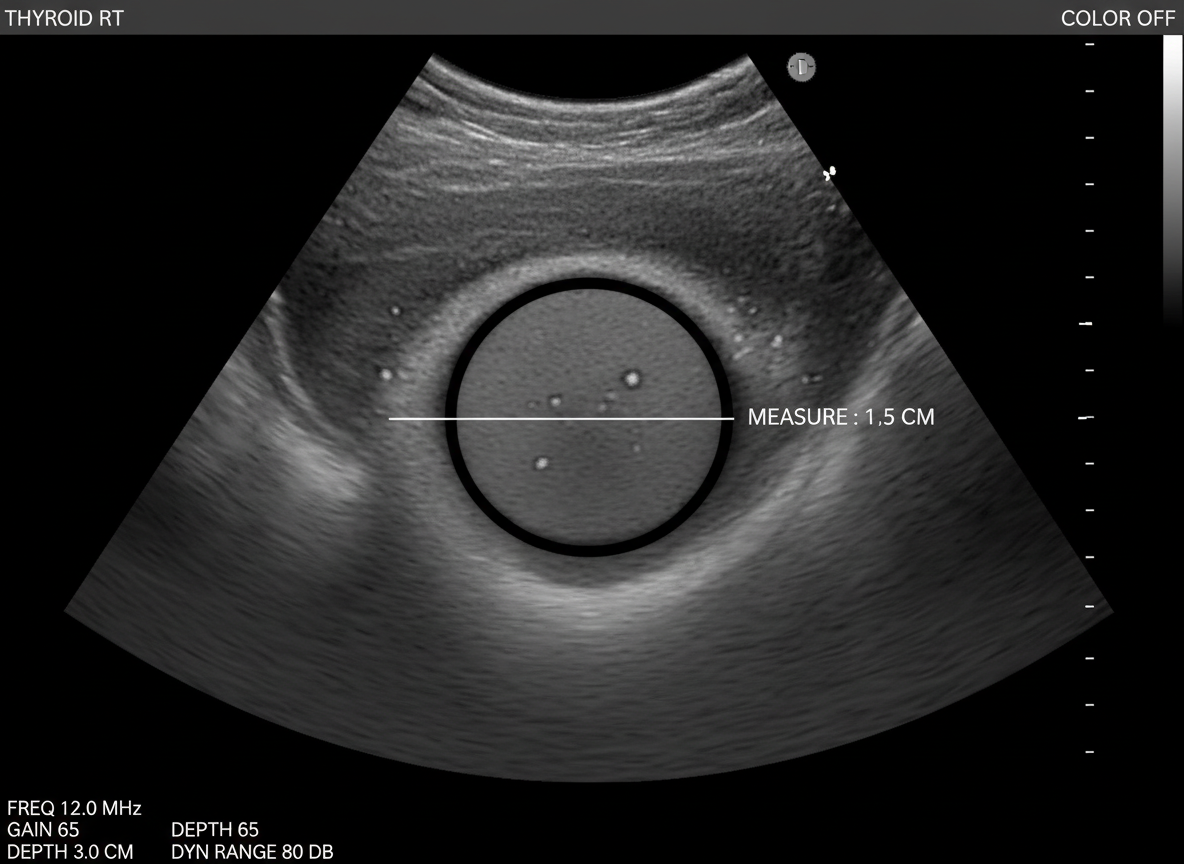

초음파 검사나 세침흡인 조직검사 같은 간단한 검사로도 충분히 확인할 수 있답니다.

갑상선암은 주로 갑상선 초음파 검사를 통해 결절을 확인하고,

의심스러운 결절이 발견되면 세침흡인 조직검사를 통해 암세포 유무를 확진해요.